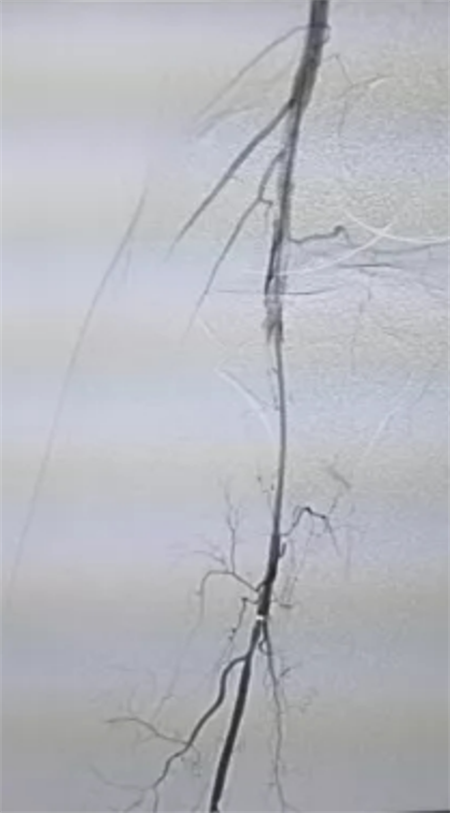

CTA见左下肢动脉栓塞